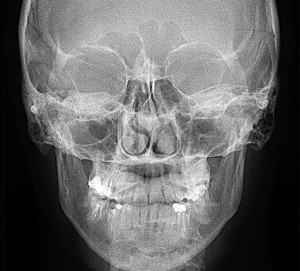

Полость носа — пространство между передней черепной ямкой и полостью рта. Полость носа разделена перегородкой на правую и левую половины и имеет передние отверстия — ноздри и задние — хоаны, ведущие в носоглотку. Каждая половина носа имеет четыре стенки • Медиальная стенка, или перегородка носа • Верхняя стенка • Нижняя стенка, или дно полости носа • Латеральная стенка

Полость носа (cavum nasi) располагается между полостью рта (снизу), передней черепной ямкой (сверху) и глазницами (латерально). Она разделена перегородкой носа на две идентичные половины, спереди посредством ноздрей сообщается с внешней средой, кзади посредством хоан — с носоглоткой. Каждая половина носа окружена четырьмя околоносовыми пазухами — верхнечелюстной (гайморовой), решетчатыми, лобной и клиновидной.